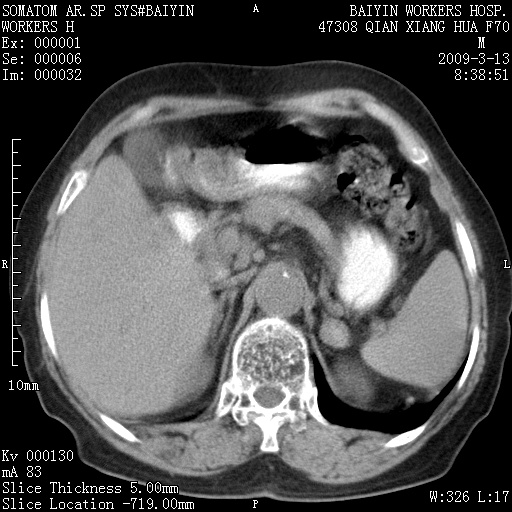

标题: CT18651:左肾上腺占位,请会诊! [打印本页]

标题: CT18651:左肾上腺占位,请会诊!

女,70岁,体检发现。

胰腺钙化灶,胰腺炎史?

左侧肾上腺结节状软组织密度影;考虑肿瘤(肾上腺腺瘤?转移瘤?)。

左侧肾上腺占位,腺瘤?不除外转移。

左侧肾上腺占位,腺瘤可能。

左侧肾上腺占位,考虑腺瘤可能。